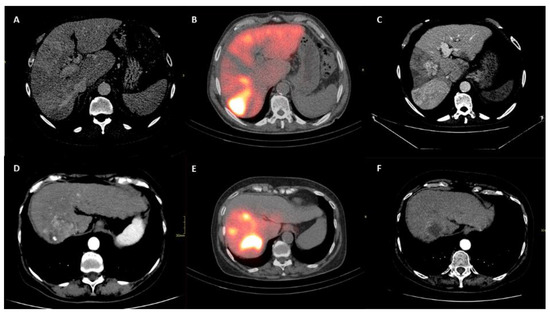

PMI was determined by measuring the major diameter and the minor diameter (measured perpendicularly to the major) of the right and of the left psoas on an axial CT scan at the time of TARE (Figure 1). A follow-up scan after TARE therapy for the assessment of PMI modification was performed at one, three and six months after the procedure (Figure 2) [14].

Figure 1. Sarcopenia status measured before the intra-arterial radioembolization in both the Sarcopenia group (A) and No-Sarcopenia group (B).